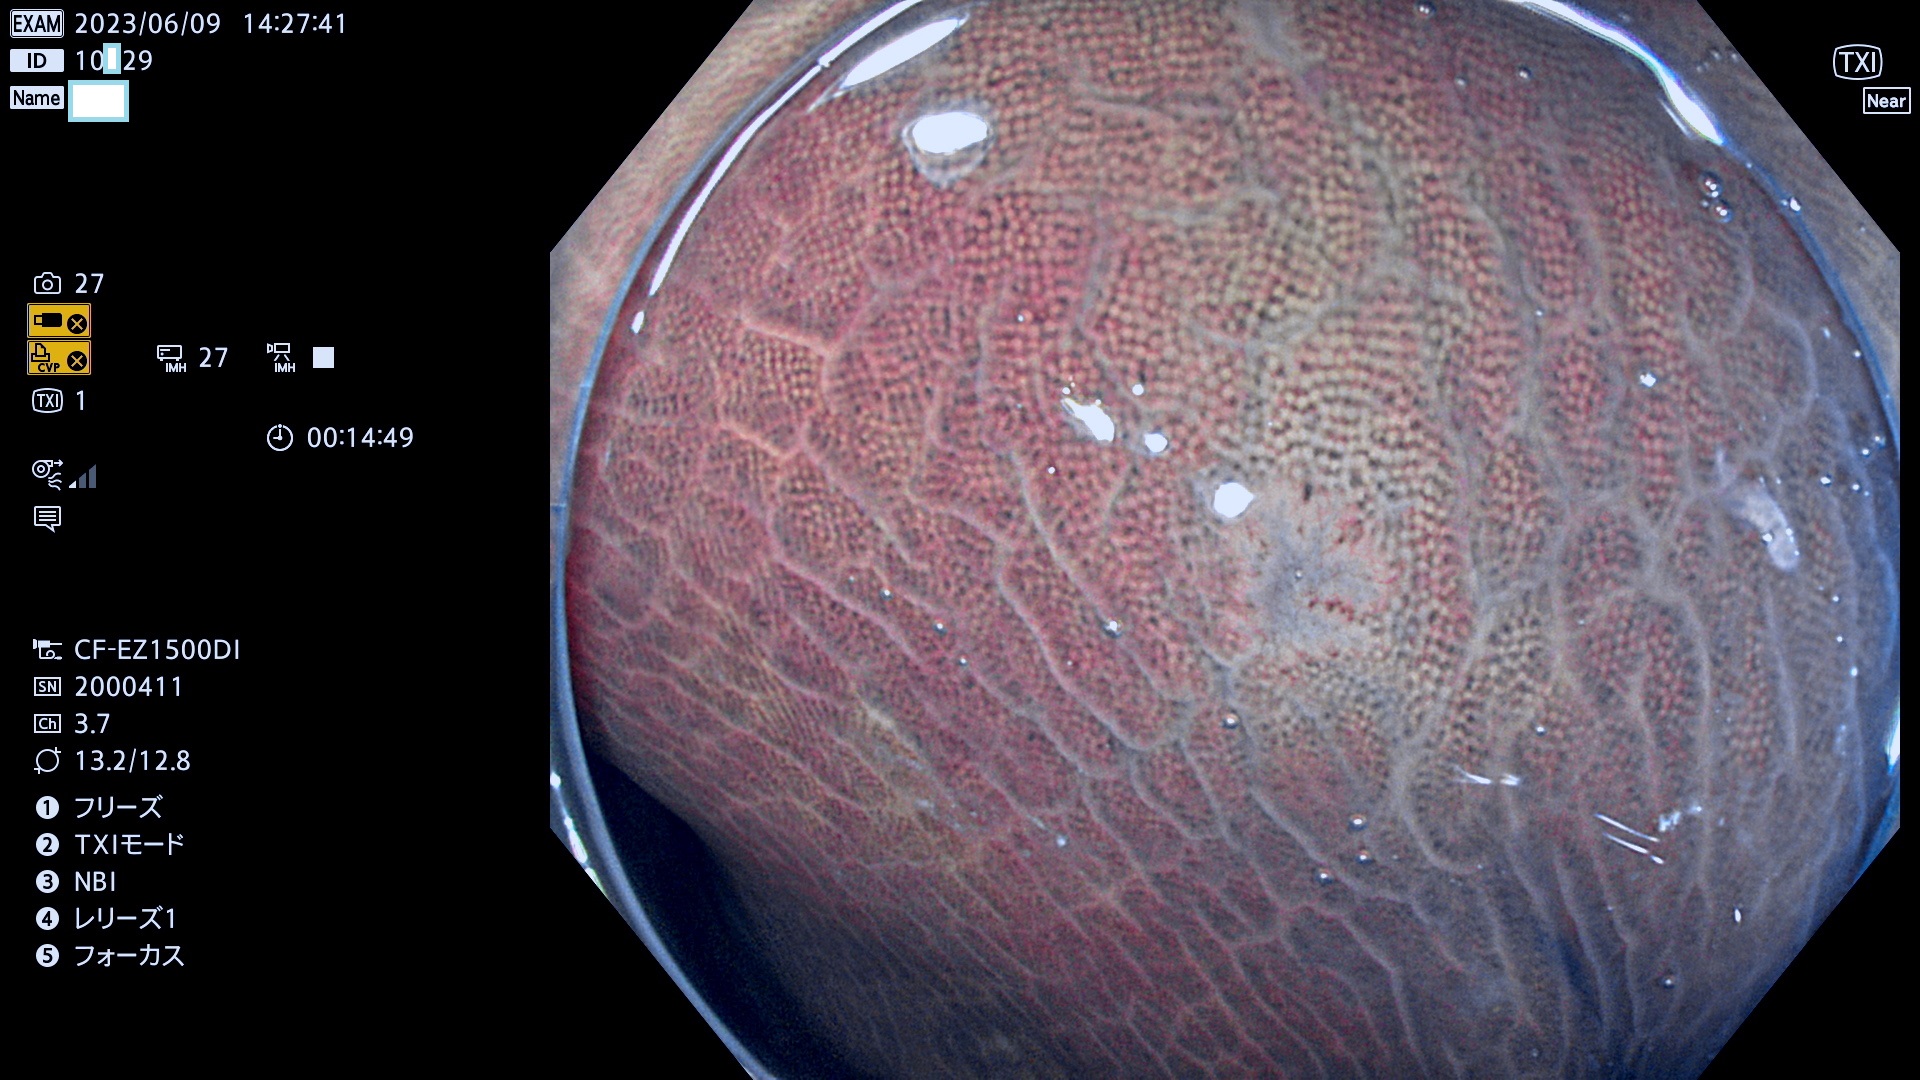

「表面型腫瘍」の中で、完全に平坦な物をUb、陥凹している物をUcと呼びます。平坦隆起型(Ua)よりも、発見が難しく危険な病変です。このタイプの発見率は「腺腫発見率」よりも、遥かに重要な意義があります。

毎週の検査(木・金・土・日)に当院の検査で発見されたUb、Uc病変を、その週の日曜の夜にUPし1週間、提示します。

抽出の対象期間 2023年6月8日(木)〜11(日)の4日間(48件の検査)